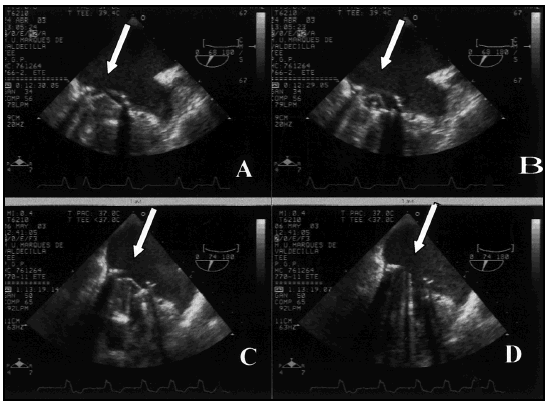

Se practicó una ETE que mostró un ventrículo izquierdo de tamaño y función normal; la prótesis valvular mitral presentaba uno de los discos bloqueados en posición de cierre provocando estenosis severa, con gradiente medio de 18 mm y área de 0,7 cm2; insuficiencia tricuspídea grado II y presión pulmonar superior a 60 mm (fig. 1).

Figura 1. A y B: sístole y diástole prefibrinolisis, se aprecia uno de los discos fijo en diástole y el otro con apertura parcial (flechas). C y D: sístole y diástole posfibrinolisis, se aprecia la apertura completa de los discos (flechas).

Una nueva ETE practicada a las 96 horas del segundo bolo de fibrinolítico, mostraba un gradiente transvalvular mitral medio de 6 mm, una insuficiencia tricuspídea ligera, presiones pulmonares inferiores a 40 mmHg y perfecta apertura de los dos discos de la prótesis con flujo normal por Doppler color (fig. 1).